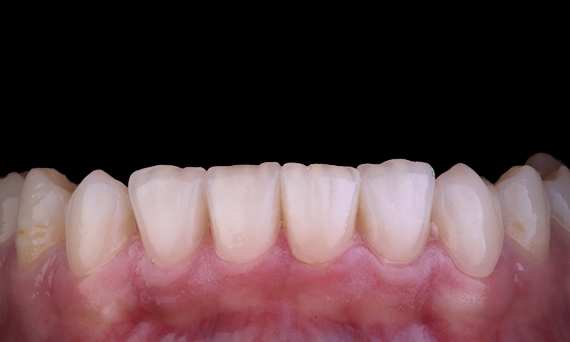

Lorsque l’on envisage de remplacer une incisive centrale maxillaire par une prothèse dentaire fixe sur implant, la sélection du cas, la planification et l’application méticuleuse des méthodes de traitement sont les clés du succès. La pose immédiate d’un implant et la restauration immédiate peuvent minimiser la perte de tissus et donner un résultat très esthétique. La pose d’un implant avec une approche entièrement guidée peut améliorer la précision de la pose, et la pose du pilier final ou de la restauration au moment de la pose de l’implant peut favoriser la stabilité des tissus.

Dr Alan Yap, Prosthodontiste, Sydney, Australie